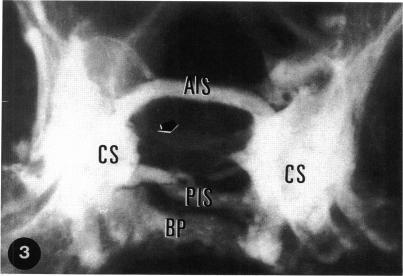

The intercavernous communications of the skull base were studied in 32 sphenoid blocks using electrolytic decalcification techniques, vascular filling, x-rays, and serial anatomical sections. In this study four intercavernous connections were found: anterior intercavernous sinus (AIS), posterior intercavernous sinus (PIS), inferior intercavernous sinus (IIS), and basilar plexus (BP). The AIS was present in 100% of the cases, with diameters ranging from 0.57 mm to 5.43 mm; in 17 cases (53.12%) it took up the whole anterior wall of the hypophyseal fossa. The PIS was also detected in 100% of the cases, and its diameters ranged from 0.71 mm to 4.14 mm. The IIS was identified in 31 cases (96.9%), assuming three different forms: plexuslike, venous lake, and mixed. The BP was found in 100% of the material analyzed; in 23 cases (71.9%) it proved to be the widest intercavernous communication.In 12 cases of this series the hypophysis was completely enveloped by venous structures, except at the level of the sellar diaphragm.